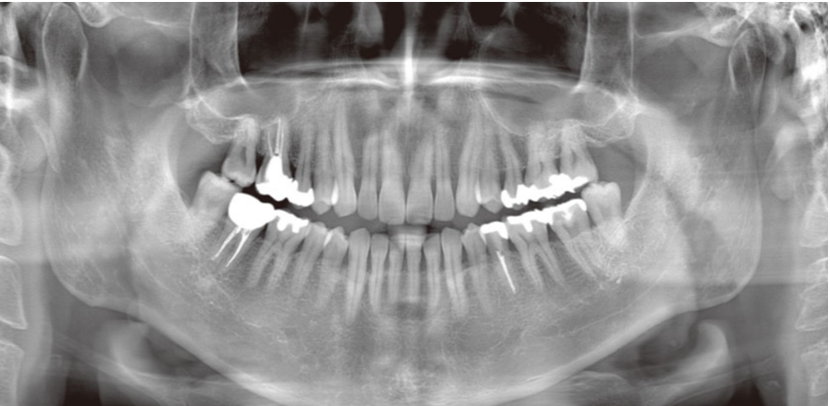

当クリニックでは、安全性と正確性が求められる歯科治療の診断にモリタ社製の最新の歯科用CT(Computed Tomography)・VeraVew X800を設置しています。

CTはレントゲン撮影の一種で撮影データをコンピュータ処理することで立体的に画像を構築できます(3D画像)。

元来のパノラマやデンタル画像に加えて、3D画像を取り入れることで、口腔内を立体的に観察し、骨の位置や量、病巣の大きさなど診断に重要な要素を把握することができます。